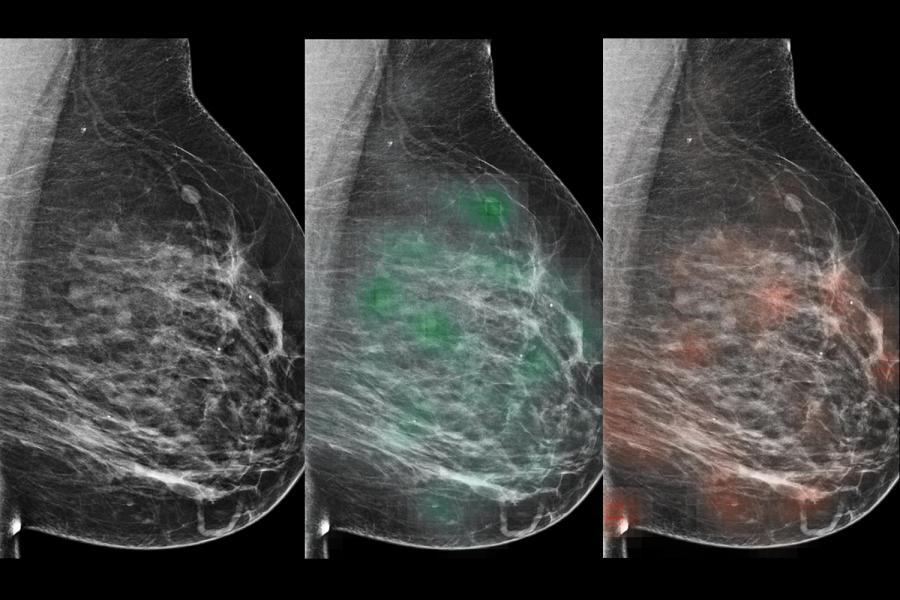

Deep Learning for Breast Cancer Detection

Our investigators develop deep neural networks to help radiologists detect breast cancer. This research involves several imaging modalities, including MRI and mammography. We tailor each algorithm to the relevant imaging method and design our networks to be human interpretable. In recent work, we have shown that neural nets can improve radiologists’ performance in breast cancer screening.